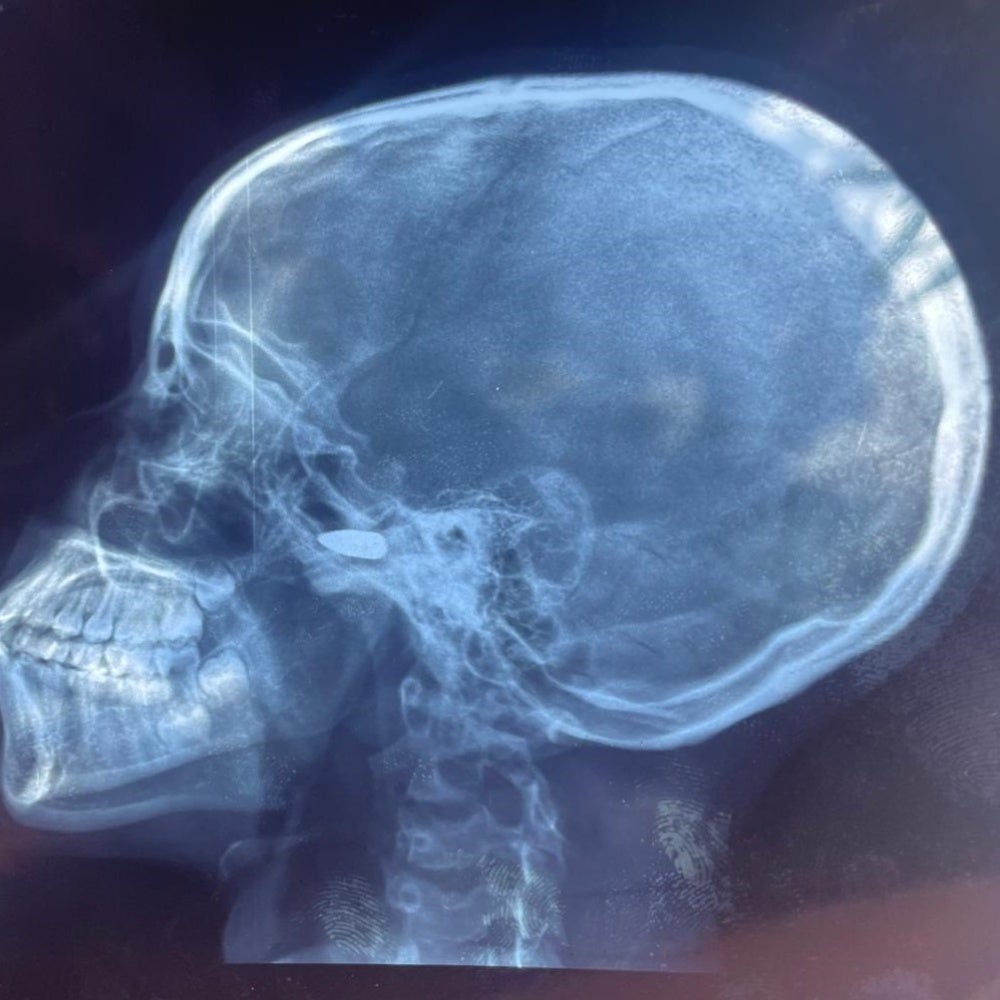

The x-ray image of a 15-year-old girl who was struck in the head by a stray bullet in Bébédja, southern Chad, on May 9, 2024 following the announcement of the provisional results of the Chad presidential elections. © 2024 Private